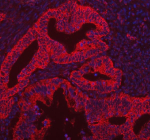

Immunofluorescent staining of CAMKK2 using anti-CAMKK2 antibody (red). CAMKK2 was detected in a paraffin-embedded section of human intestinal cancer tissue. Heat mediated antigen retrieval was performed in EDTA buffer (pH 8.0, epitope retrieval solution). The tissue section was blocked with 10% goat serum. The tissue section was then incubated with 5 ug/ml rabbit anti-CAMKK2 antibody overnight at 4oC. Cy3-conjugated Anti-rabbit IgG Secondary antibody was used as secondary antibody at 1:500 dilution and incubated for 30 minutes at 37oC. The section was counterstained with DAPI (blue). Visualize using a fluorescence microscope and filter sets appropriate for the label used.